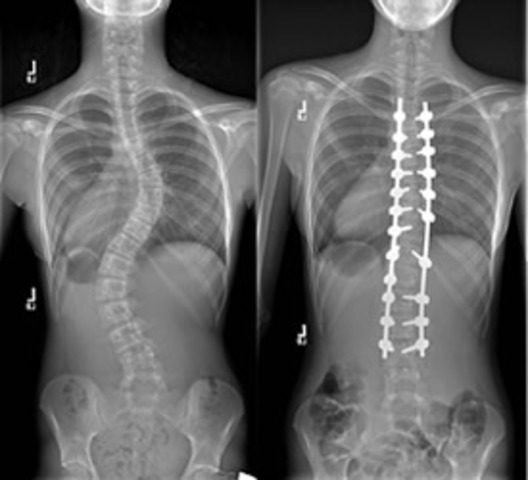

• I figured out I had scoliosis

I figured out I had scoliosis

I had pain in my back and someone said my back was curved. I went to the doctors and they told me the news. My heart felt liked it stopped. It was a big impact on my life.

• I got my scoliosis surgery

I got my scoliosis surgery

Before my surgery I had to wear a brace. I was really scared and after my surgery I had to learn how to do things differently. It was difficult for me to get used to my new body.